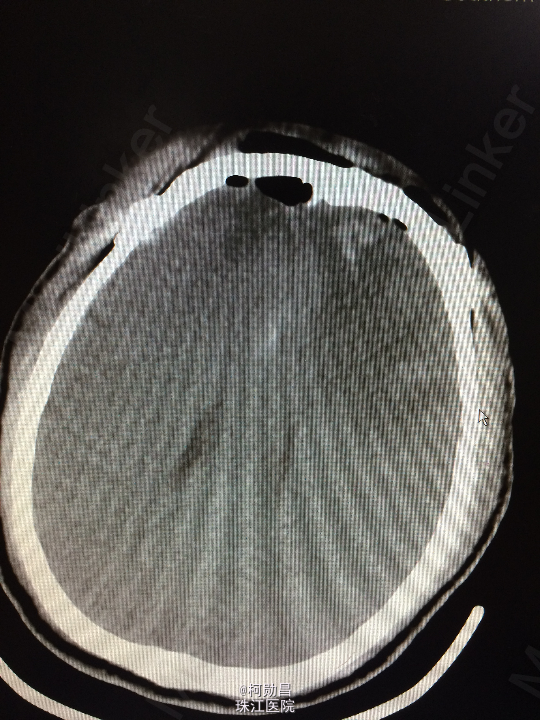

主诉:头痛伴左眼视力下降半年 病史:患者46岁男性,缘于半年前无明显诱因出现头痛,当时未予特殊处理,后症状进行性加重,并发左眼视力下降,于当地医院行头颅CT及MR检查提示颅内占位,为进一步治疗而入我院。 既往病史:5年前曾患鼻咽癌

查体:神志清楚,对答流利,左侧眼裂变小,左侧瞳孔散大,直径4mm,对光反射迟钝,左眼视力下降。右侧正常。 辅助检查:头颅MR提示前颅底筛沟通病变

诊断:鼻咽癌脑转移 处理:全麻下行颅筛沟通占位切除术,术后病理提示:鼻咽非角化鼻咽癌脑转移